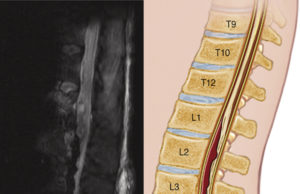

Improvements in techniques of distal organ protection decreased the risk of spinal cord injuries (SCIs) from 30% to <5% with open repair of extent...